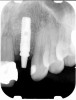

Figure 2 Identification of sufficient inter-radicular space: The radiographic representation of inter-radicular space (Fig 2) reveals abundant space for a single-tooth implant; at the alveolar crest,

> 6 mm of interproximal space is available for placeme

Figure 3 Identification of sufficient inter-radicular space: The radiographic representation of inter-radicular space (Fig 2) reveals abundant space for a single-tooth implant; at the alveolar crest,